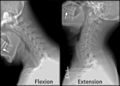

- الفقرة العنقية الأولى أو الفهقة Atlas: وهي أولى فقرات العمود الفقري وتكون حلقية الشكل، وتربط الجمجمة ببقية العمود الفقري. وليس لها جسم فقري لأن جسمها قد التحم مع الفقرة التي تليها (أثناء نمو الجنين). سطح الفهقة يكون بيضاوي الشكل أو على شكل كلية ويتمفصل نتوئين من الجمجمة. سطحها السفلي يكون مستديراً. اما شوكتها فهي صغيرة جداً وهي بشكل مرتفع صغير. لأنها لو كانت كبيرة لكانت قد أعاقت حركة الجمجمة خاصة إلى الخلف (أي عند النظر لأعلى)، بينما يكون النتوءان المستعرضان طويلان وهي تعمل كعتلة للعضلات التي تدير الرأس.

- الفقرة العنقية الثانية أو المحور Axis: لها نتوء مميز وهو ينشأ من جسم هذه الفقرة ومنها يرتفع إلى أعلى بشكل عمودي ليمر عبر حلقة الفهقة ويشده في مكانه رابط يسمى الرابط المستعرض. وتدور وتستقر فقرة الفهقة على فقرة المحور.